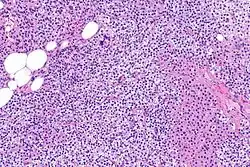

Bioquímicamente, hay cambios en la función entre las glándulas paratiroides hiperplásicas normales y nodulares. Estos cambios implican la expresión de protooncogenes y activación de rutas proliferativas, mientras que se inactivan las rutas apoptóticas.[28] En el tejido paratiroideo nodular, el aumento de la expresión de TGF-α, un factor de crecimiento, y EGFR, su receptor, da como resultado una proliferación agresiva y una mayor regulación a la baja de los receptores de vitamina de, que actúan para suprimir las secreciones hormonales.[25][8] Además, se aprecia que el marcador de proliferación Ki67 se expresa en gran medida en el estado hiperplásico nodular secundario. Se ha destacado que los genes supresores de tumores se encuentran silenciados o degradados en el tejido paratiroideo hiperplásico nodular. Uno de estos genes, p53, regula múltiples rutas de supresión de tumores y en la oncogénesis puede ser degradado por b-catenina. Esta ruta está en parte mediada por CACYBP, que se expresa en gran medida en la hiperplasia paratiroidea nodular.